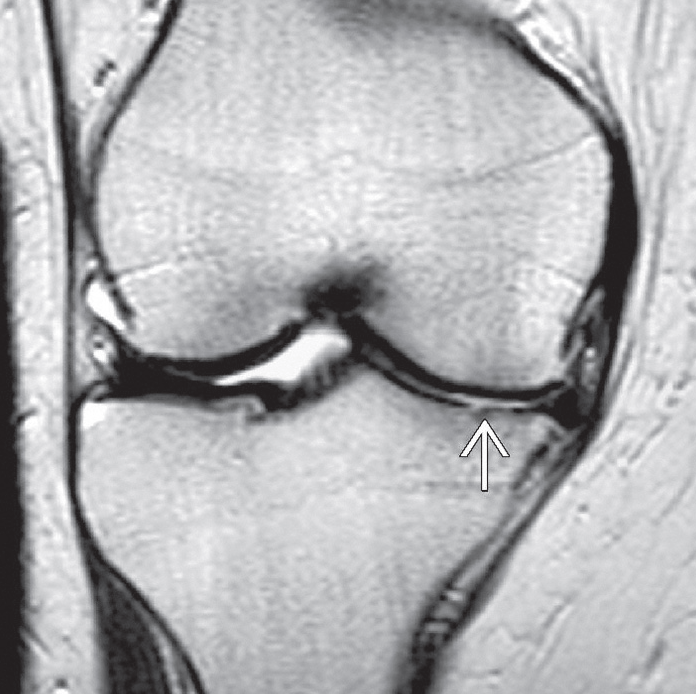

Ameliyat öncesinde hastanın şikayeti ve hikayesi dinlenir. Muayenede diz hareketleri, stabilite ve dizin gücü değerlendirilir. Ameliyat planlaması için röntgen filmleri çekilmelidir. Bazen dizdeki kemik ve yumuşak dokuların durumunu belirlemek için kan testleri veya manyetik rezonans görüntüleme (MRI) taraması gibi ileri görüntülemeler gerekebilir.

Dizin iç kısmında kıkırdak incelmiş ve buna bağlı olarak eklem aralığı daralmış.